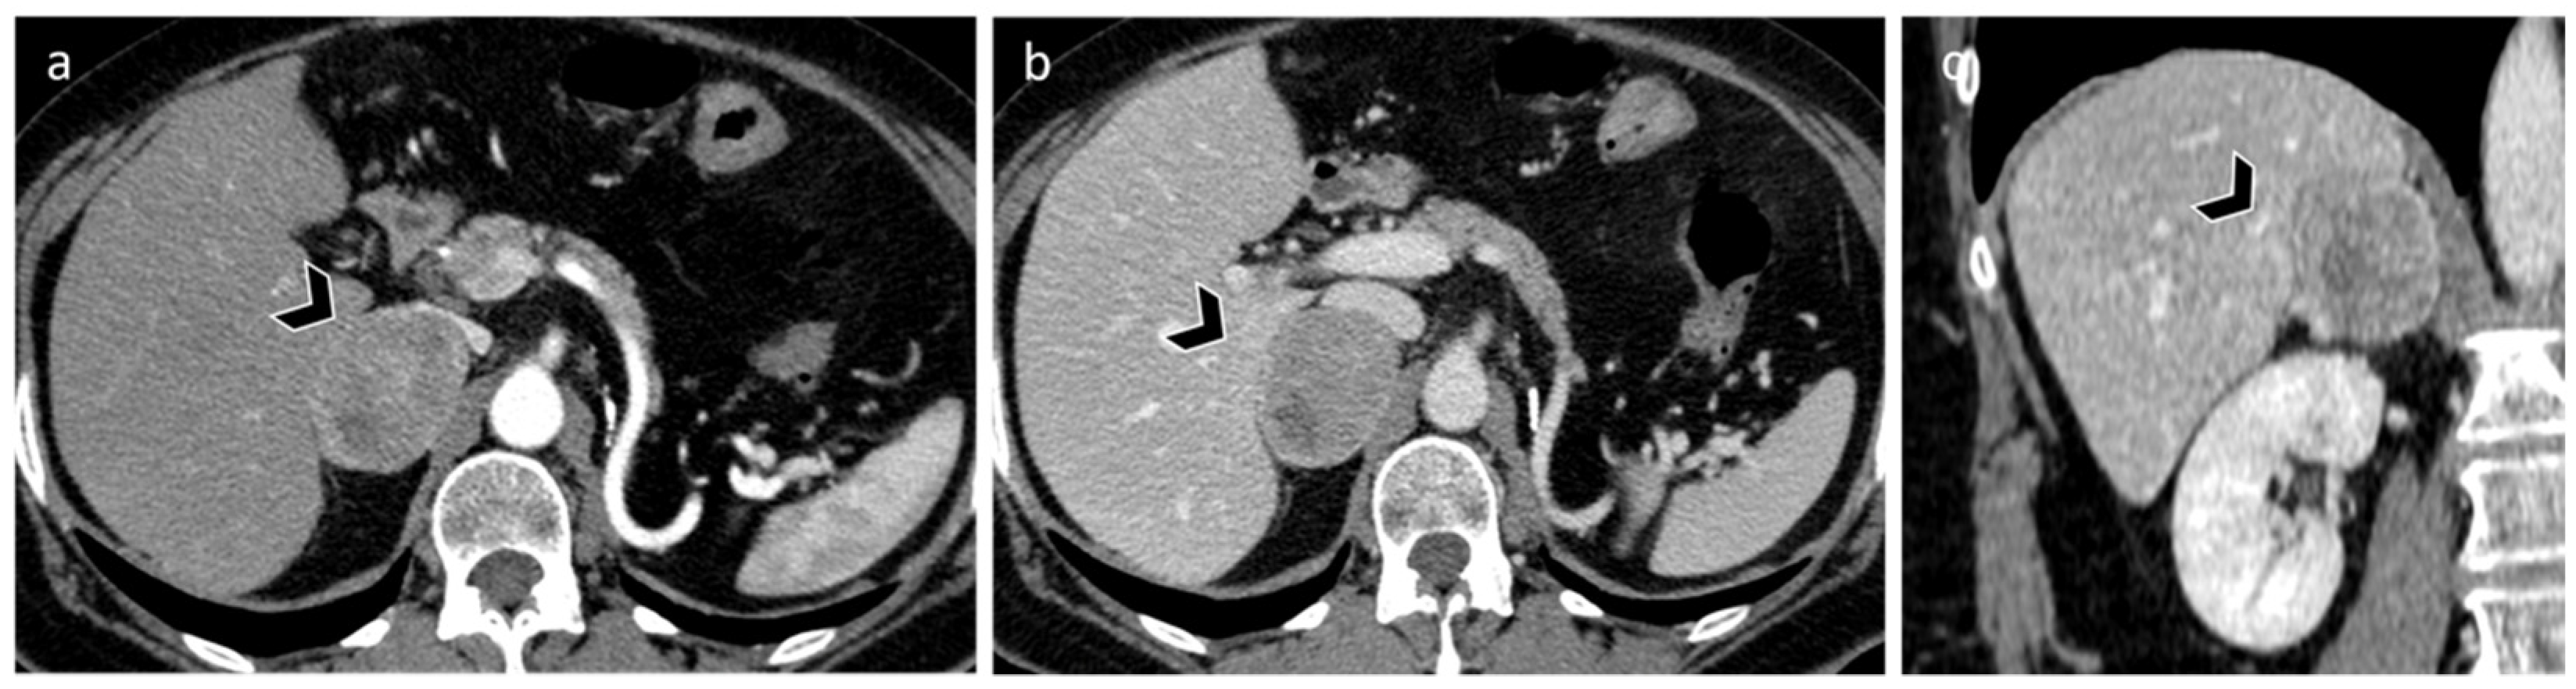

3.2. Metastasis